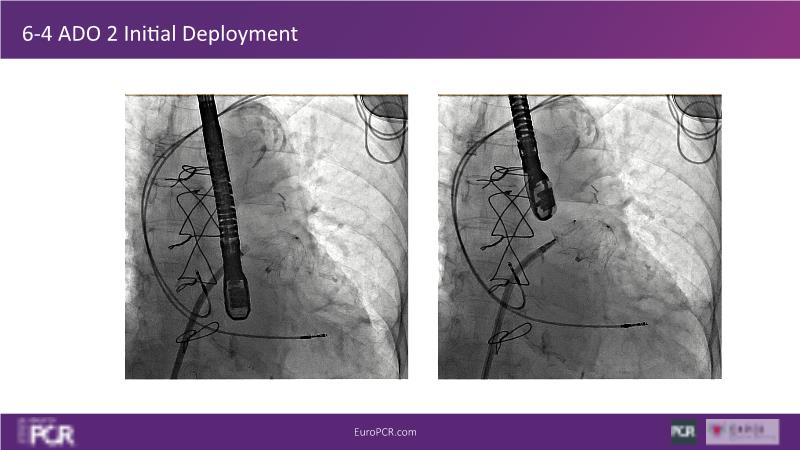

Explore this session to discover the latest innovations in interventional cardiology images, including the benefits of artificial intelligence and angio-CT in PCI/SHD procedures. Learn about Alphenix Evolve and the initial experiences with AI imaging in daily cathlab practice, alongside intraprocedural angio-CT guided LAAO, and engage in discussions on meaningful tools that can transform patient care.